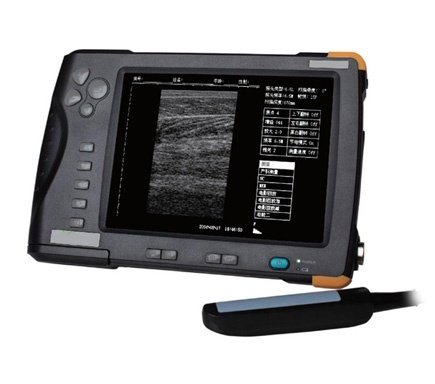

Portable Veterinary Ultrasound Scanner 2-10MHz Waterproof SIFULTRAS-4.2

Portable Veterinary Ultrasound Scanner 2-10 MHz Waterproof SIFULTRAS-4.2

- Image smoothing, filtering, edge enhancement, frame correlation, linear interpolation, and other processing, the image is crisp and clear in high resolution.

- 7-inch TFT screen.

- Small and lightweight (at-home ultrasound).

- Display size: 7-inch TFT.

- Overall size: 216mm×147mm×27mm.

- Total weight: 950g(with battery).